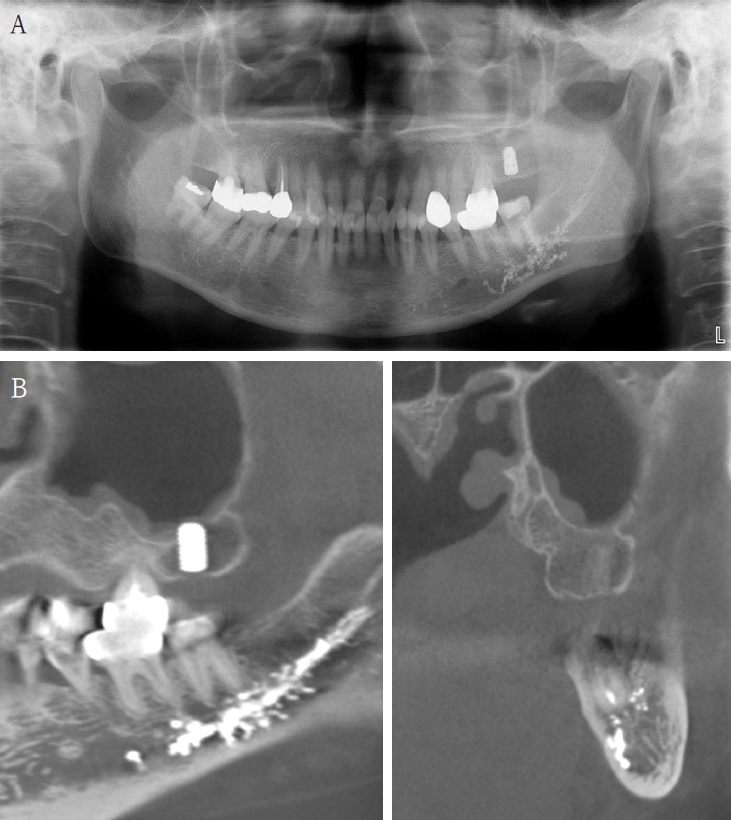

A 63-year-old female presented three days after endodontic treatment of the mandibular left second molar (#37) with symptoms of numbness in the left lower lip and gingiva. A panoramic radiograph and cone-beam computed tomography (CBCT) revealed extrusion of Calcipex II into the mandibular canal (Fig. 1). Initial neurosensory testing demonstrated mild hypoesthesia. She was admitted for foreign body removal and neurorrhaphy under general anesthesia. A post-operative panoramic radiograph confirmed the removal of the foreign body (Fig. 2). Although surgical curettage and neurorrhaphy were performed on the fourth day post-onset, no significant symptom relief was noted at the one- and two-week follow-ups. At the three-month follow-up, she reported persistent numbness with mild neuropathic discomfort but no marked improvement. A follow-up neurosensory exam is scheduled for the six-month check-up.